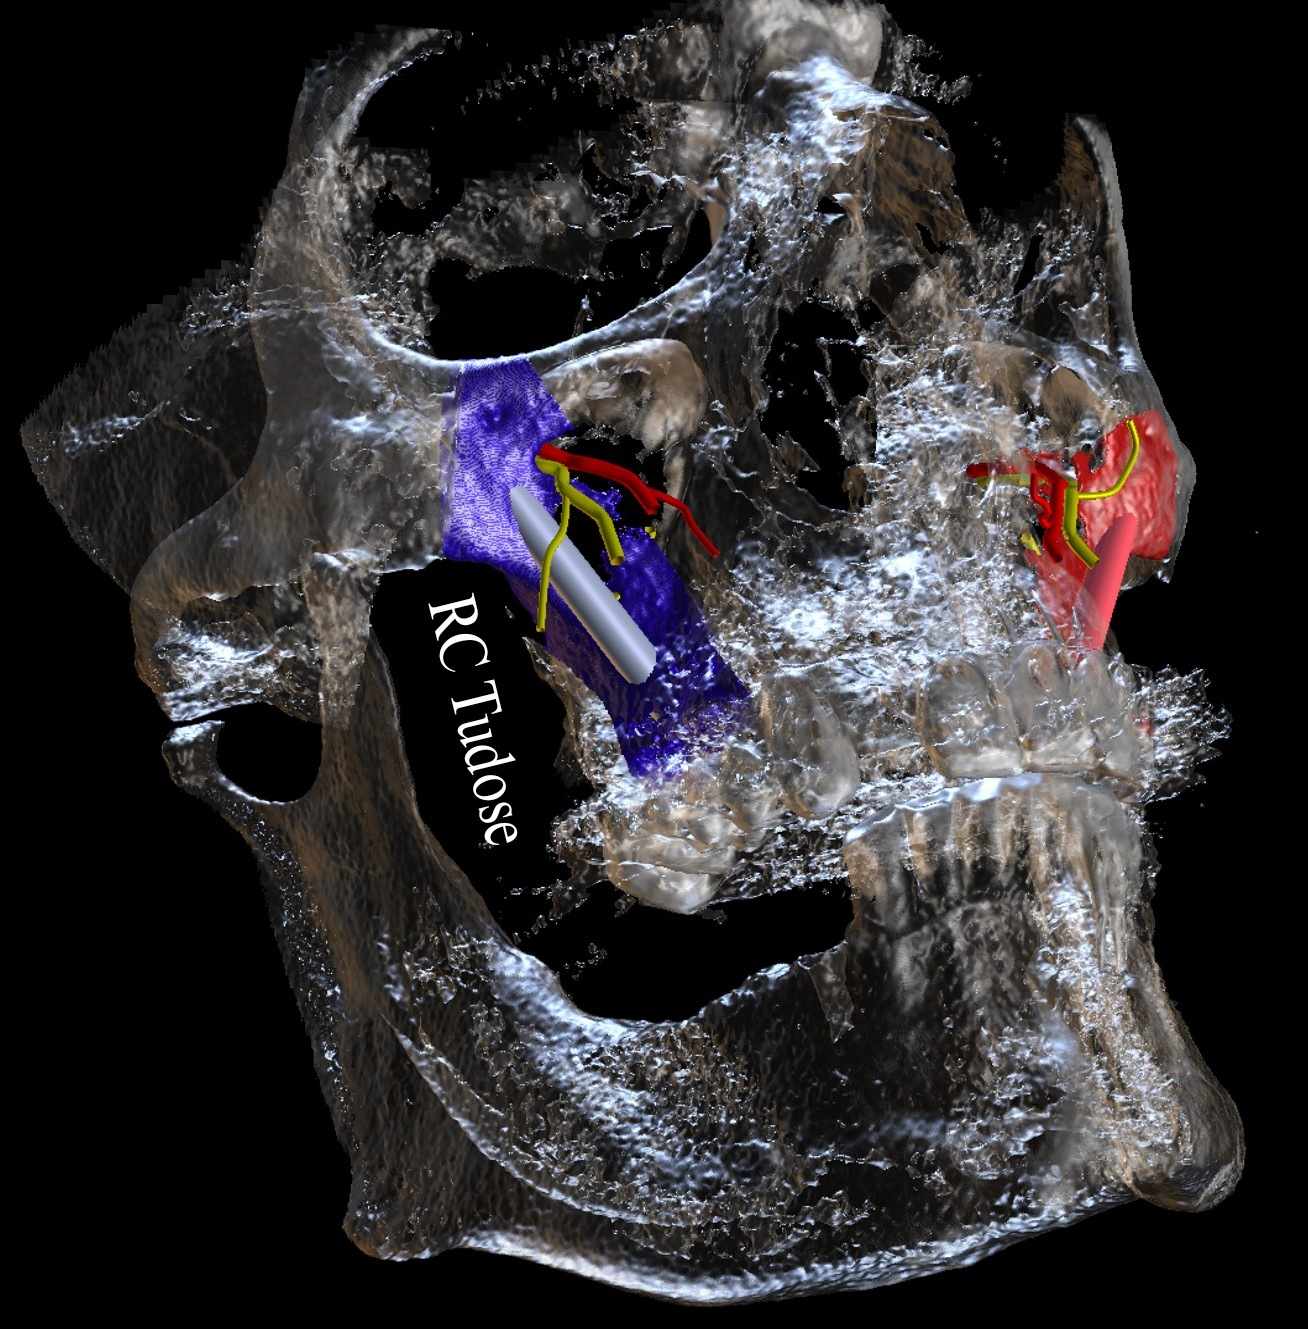

Oral Presentation - CBCT assessment of the greater palatine canal

Oral Presentation - The Zygomatic Implant: An anatomical view of the potential risks